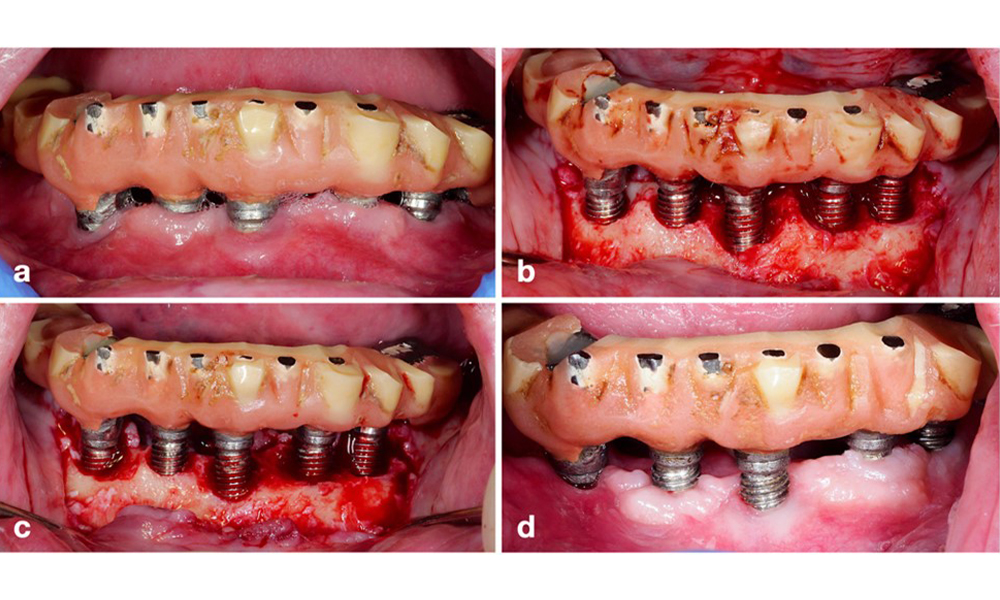

A resective approach (i.e., gingivectomy and/or apically positioned flap, with/without bone re-contouring) should be chosen in cases with mainly horizontal bone loss or wide defects, where the potential for bone regeneration is limited (figure 11).

For implants with a modified surface and in regions where bone regeneration is unlikely, implantoplasty should be considered. This procedure involves removing implant threads and smoothing of the micro-structured implant surface with rotating instruments (figure 12). This approach facilitates comprehensive decontamination of the implant surface, and – most importantly – improves postoperative biofilm control (Bertl and Stavropoulus 2021; El Chaar et al. 2020; Geremias et al. 2017). Due to a lack of sufficient clinical evidence there is controversy about the role of implantoplasty (Herrera et al. 2023; Ramanauskaite et al. 2021), however the concerns about inducing inflammation by the inevitable deposition of titanium particles and the increased risk of implant fracture due to reduction of implant strength have not been substantiated (Stavropoulos et al. 2019).